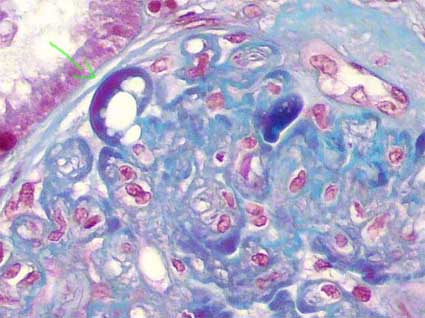

FSGS perihilar variant

In order to diagnose this variant we must exclude the hypercellular variant and the collapsing variant. In other words, if there are many glomeruli with perihilar lesions, but at least one with hypercellular or collapsing lesion, we do not diagnose the perihilar variant, but like these last ones respectively. If there are a glomerulus with “tip lesion” it does not exclude this category.

Defining criteria include both of the following: a) there must be at least 1 glomerulus with perihilar hyalinosis, with or without sclerosis; and b) more than 50% of glomeruli with segmental lesions must have perihilar sclerosis and/or hyalinosis.

Other glomeruli may show lesions as described in FSGS NOS. In some cases there is some degree of mesangial proliferation, and lipid vacuoles and hypertrophy or hyperplasia of podocytes may be identified, although this last finding is less frequent than in other variants.

This type of lesion is common in patients with secondary forms of FSGS mediated by an adaptive response to nephron loss or glomerular hypertension: in association with obesity, cyanotic congenital heart disease, reflux nephropathy, renal agenesis, or any renal disease with reduced number of functioning nephrons.

Figure 8. In this microphotography, we see a glomerular arteriole (blue arrows), in the tuft there are hyaline segments in its vascular pole (green arrows). The perihilar variant characterize by al least one glomerulus with perihilar hyalinosis (as seen in this image), accompanied or not by sclerosis, and more than 50% of glomeruli with segmental lesions must have sclerosis and/or perihilar hyalinosis. There must not be glomeruli with collapsing or hypercellular lesions. (Mason’s trichrome, X400).